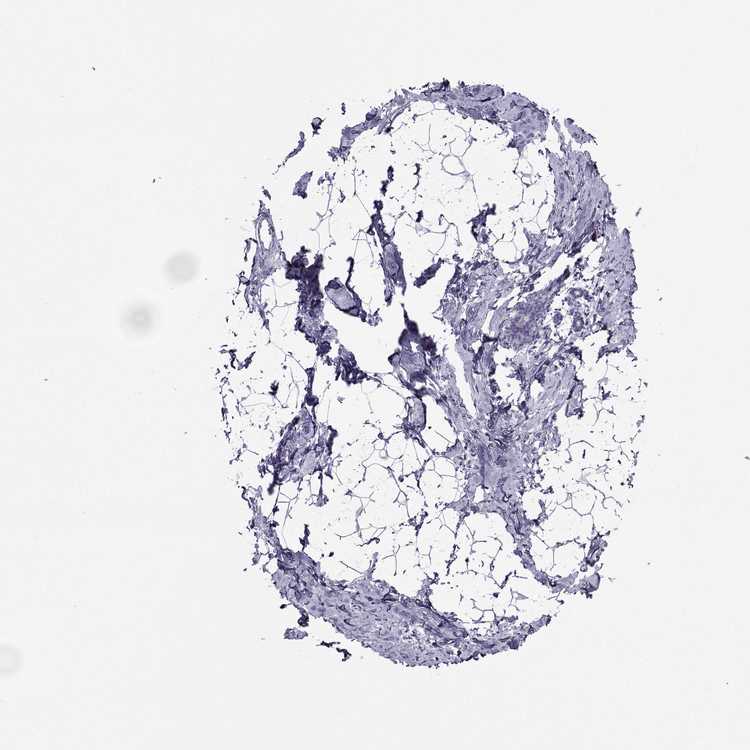

BREAST - Antibody stainingi

Antibody staining in the annotated cell types in the current human tissue is reported as not detected, low, medium, or high, based on conventional immunohistochemistry profiling in selected tissues. This score is based on the combination of the staining intensity and fraction of stained cells.

Each image is clickable and will lead to virtual microscopy that enables deeper exploration of all samples and also displays staining intensity scores, fraction scores and subcellular localization as well as patient and tissue information for each sample.

Antibody HPA045385Antibody HPA073644Antibody HPA073656

Adipocytes Not detectedNot detectedNot detected

Glandular cells LowNot detectedNot detected

Myoepithelial cells LowNot detectedNot detected